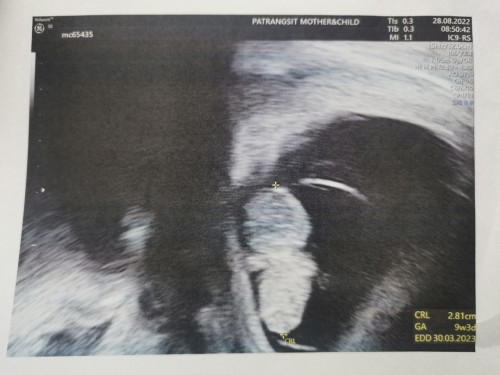

บ้านนี้ไปเมื่ออาทิตย์ที่แล้วจะเห็นเฉพาะถุงตั้งครรภ์เหมือนกันค่ะ แต่เมื่อวานครบอีก1สัปดาห์แม่ใจร้อนทนไม่ไหว ไปอีกคลินิกนึง เห็นหัวใจและตัวน้องแล้วค่ะ 7วีค6วัน ค่ะ

ลองรออีกสักหน่อยนะคะแม่ บ้านนี้ซาวด์ครั้งแรก9w หมอคลำหน้าท้องบอกว่าเริ่มสัมผัสได้ แต่หมอพิจารณาซาวด์ผ่านช่องคลอดให้ค่ะ ชัดแจ๋วเลยค่ะ ได้ยินเสียงหัวใจดังมาก